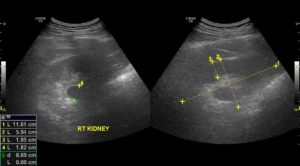

Структурные аномалии этих органов, такие как уплотнение почек, выявляются на УЗИ

Уплотнение — это естественная реакция на воспаление. Уплотнение проявляется в ходе ультразвуковой диагностики, как зона с повышенной эхогенностью, что отличается от волновых характеристик других участков почки.

Также УЗИ устанавливает площадь, локализацию, степень неоднородности тканей и контуры уплотнения, а также другие возможные деформационные изменения.

Как выглядит уплотнение в почках на УЗИ

Изменение эхогенности ЧЛС указывает на их уплотнение. Если стенки собирательной системы утолщаются, интенсивность отражения ультразвуковой волны от их поверхности увеличивается. Во время обследования УЗИ-специалист обязательно заметит: